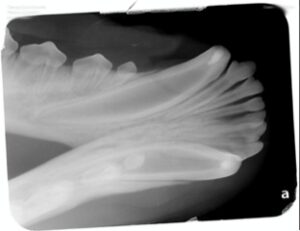

To grasp the importance of this procedure, let’s begin with a brief anatomy lesson. The “pulp” of a tooth contains blood vessels, nerves, and connective tissue, vital for its function. Dentin, the second layer, constitutes a substantial portion of the tooth’s structure and becomes denser as pets age. Meanwhile, enamel, the outer layer, provides durability. Young pets have wider pulp chambers, rendering their teeth more vulnerable to injury.

When a tooth experiences trauma, such as fractures involving dentin or pulp, it becomes sensitive and painful. Prompt treatment is essential to prevent infection and alleviate discomfort. Vital pulp therapy emerges as an optimal solution in such cases, especially when the trauma is recent or intentional during dental procedures.

2. Malocclusion Treatment: In cases where misalignment risks tooth or tissue damage, this treatment and crown reduction prevent further harm, particularly in young pets with immature permanent teeth.